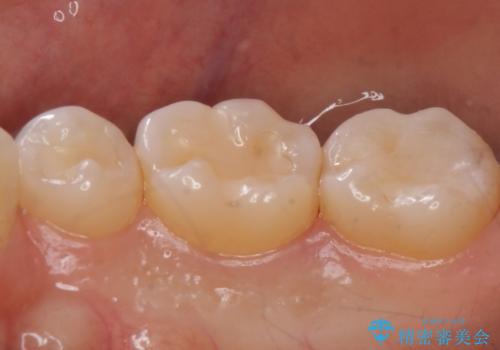

奥歯が欠けた セラミックインレーでの修復後、ナイトガード装着

- 右下の奥歯が欠けたとのことで来院されました。

欠けた部分にはセラミックインレーで修復処置を行い、今後の破折リスクを抑えるためにナイトガードを製作していきます。